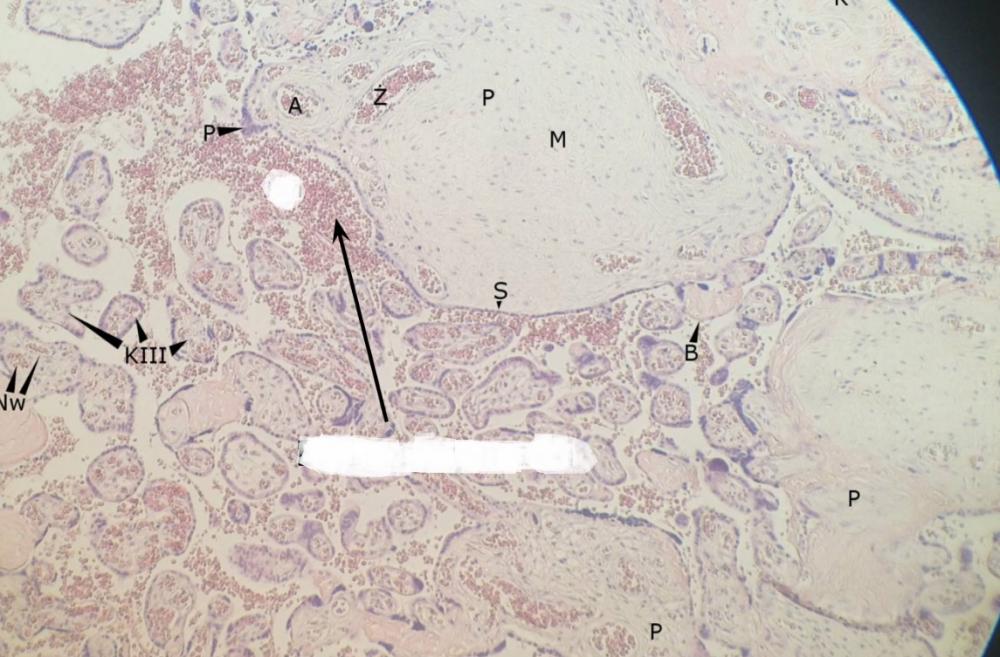

pnie kosmówkowe (łożysko, płyta kosmówkowa)

kosmki końcowe (łożysko, płyta kosmówkowa)

syncytiotrofoblast (łożysko, płyta kosmówkowa)

węzły syncytiotrofoblastu - jądra komórkowe (łożysko, płyta kosmówkowa)

płytki nabłonkowo-naczyniowe - cytoplazma bez jąder (łożysko, płyta kosmówkowa)

erytrocyty matki (łożysko, płyta kosmówkowa)

erytrocyty płodu (łożysko, płyta kosmówkowa)

przegroda łożyskowa (łożysko, płyta kosmówkowa)

komórki doczesnowe (łożysko, płyta kosmówkowa)

komórki kotwiczące (łożysko, płyta kosmówkowa)

naczynia włosowate (łożysko, płyta kosmówkowa)